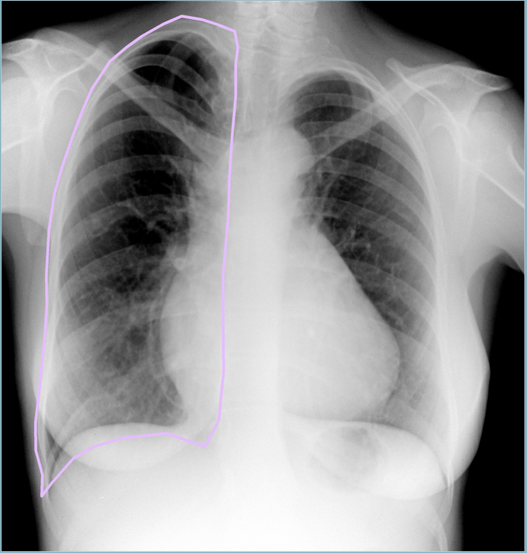

- Тесты на качество разметки. Некоторые косяки разметки вполне можно ловить автоматически. К примеру, иногда крепкая рука врачей дрожит и кликает не на тот класс объекта. На снимке снизу врач разметил перелом размером с лёгкое. Взгляд на гистограмму размеров объектов класса “Перелом” в обучающей выборке позволяет понять, что тут могла закрасться ошибка… Такие снимки можно автоматически помечать для последующего ревью.

Сломанное лёгкое

Обычно ломают небольшую часть кости